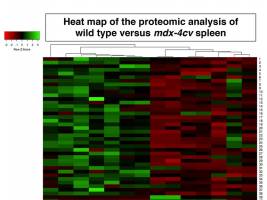

Biowissenschaften - Gesundheit - 27.08.2020

Die Duchenne-Muskeldystrophie (DMD) ist die im Kindesalter am häufigsten auftretende Muskelerkrankung, die X-chromosomal rezessiv vererbt wird. Typisch ist ein fortschreitender Muskelschwund. Die Erkrankung führt häufig schon vor dem dritten Lebensjahrzehnt zum Tode. Wissenschaftler der Universitäten Maynooth (Irland) und Bonn haben bei an Duchenne erkrankten Mäusen einen Zusammenhang zwischen dystrophischen Muskeln und Lymphsystem gefunden.